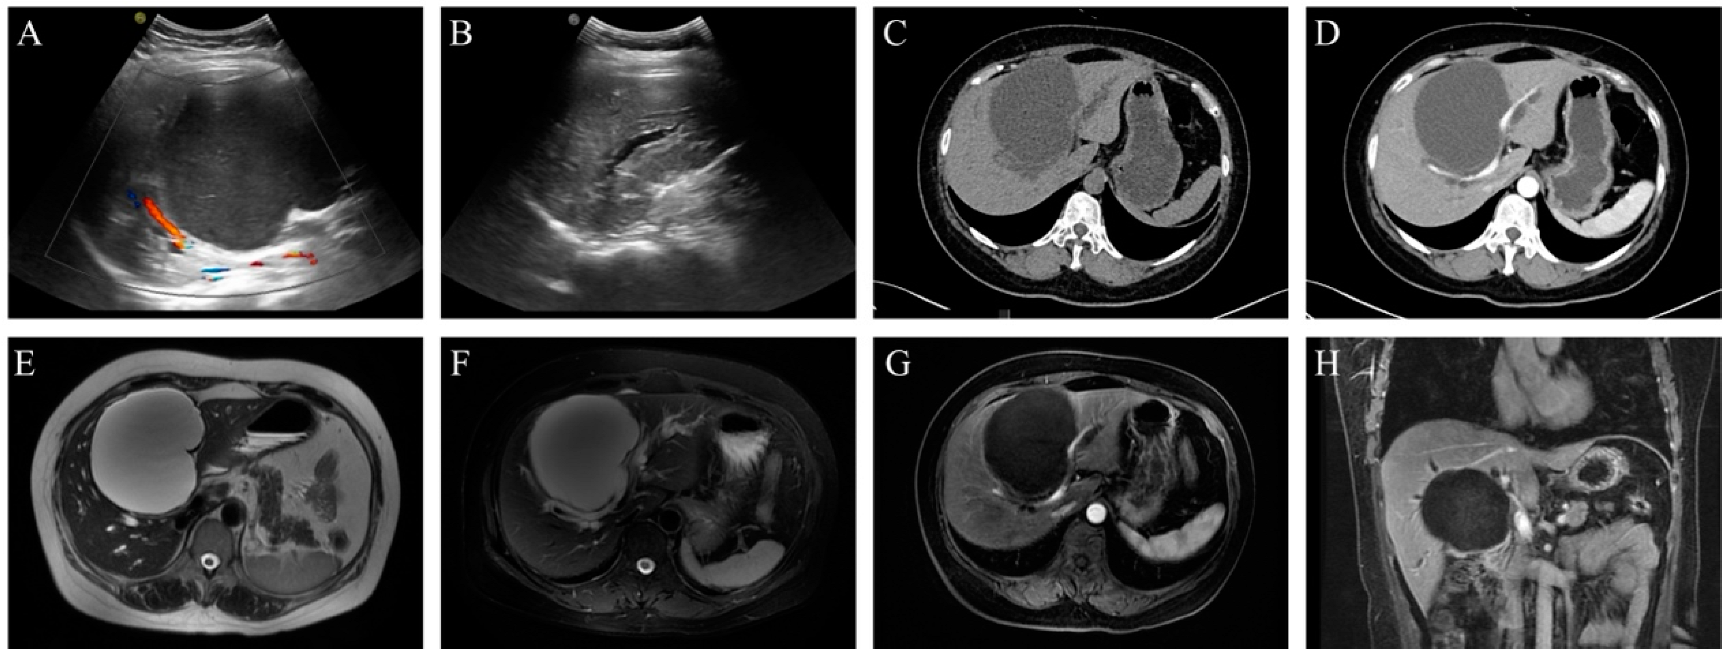

| 24 | 48 | F | 136.7 | 96.9 | Hilar | 11.2 | Jaundice, abdominal pain | Segment IV resection | 12 months | Alive without recurrence | Present Case | 2024 |